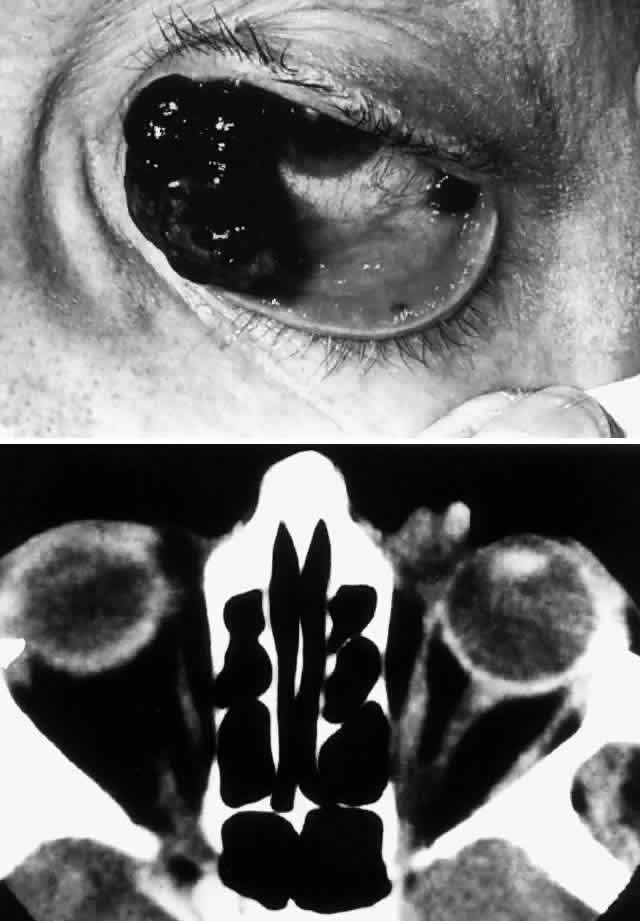

Fig. 12. An 81-year-old white woman had been aware of a pigmented lesion in the left caruncular region for 18 months. It had gradually increased in size and had bled on several occasions. In addition, she was aware of a lump on the left side of her neck for 6 weeks. On examination, a large, nodular, pigmented medial conjunctival lesion associated with thickening and induration of the tarsal conjunctiva was noted, as was a nodular satellite lesion in the temporal aspect of the inferior fornix due to local lymphatic spread (A). There was lateral displacement of the globe and some limitation of abduction. Axial CT scan demonstrates the irregularly shaped mass in the anterior orbit involving the insertion of the medial rectus muscle (B). The patient refused exenteration and underwent local resection, cryotherapy, mucous membrane graft, and radical neck dissection. Of 31 neck nodes removed, 2 were positive for metastatic disease. Nodular recurrence developed in her left jaw, and the patient died 1 year after presentation without evidence of local ocular recurrence. (Rootman J, Ragaz J, Cline R, Lapointe JS: Metastatic and secondary tumors of the orbit. In Rootman JR (ed): Diseases of the Orbit: A Multidisciplinary Approach, pp 405–427. Philadelphia, JB Lippincott, 1988.)